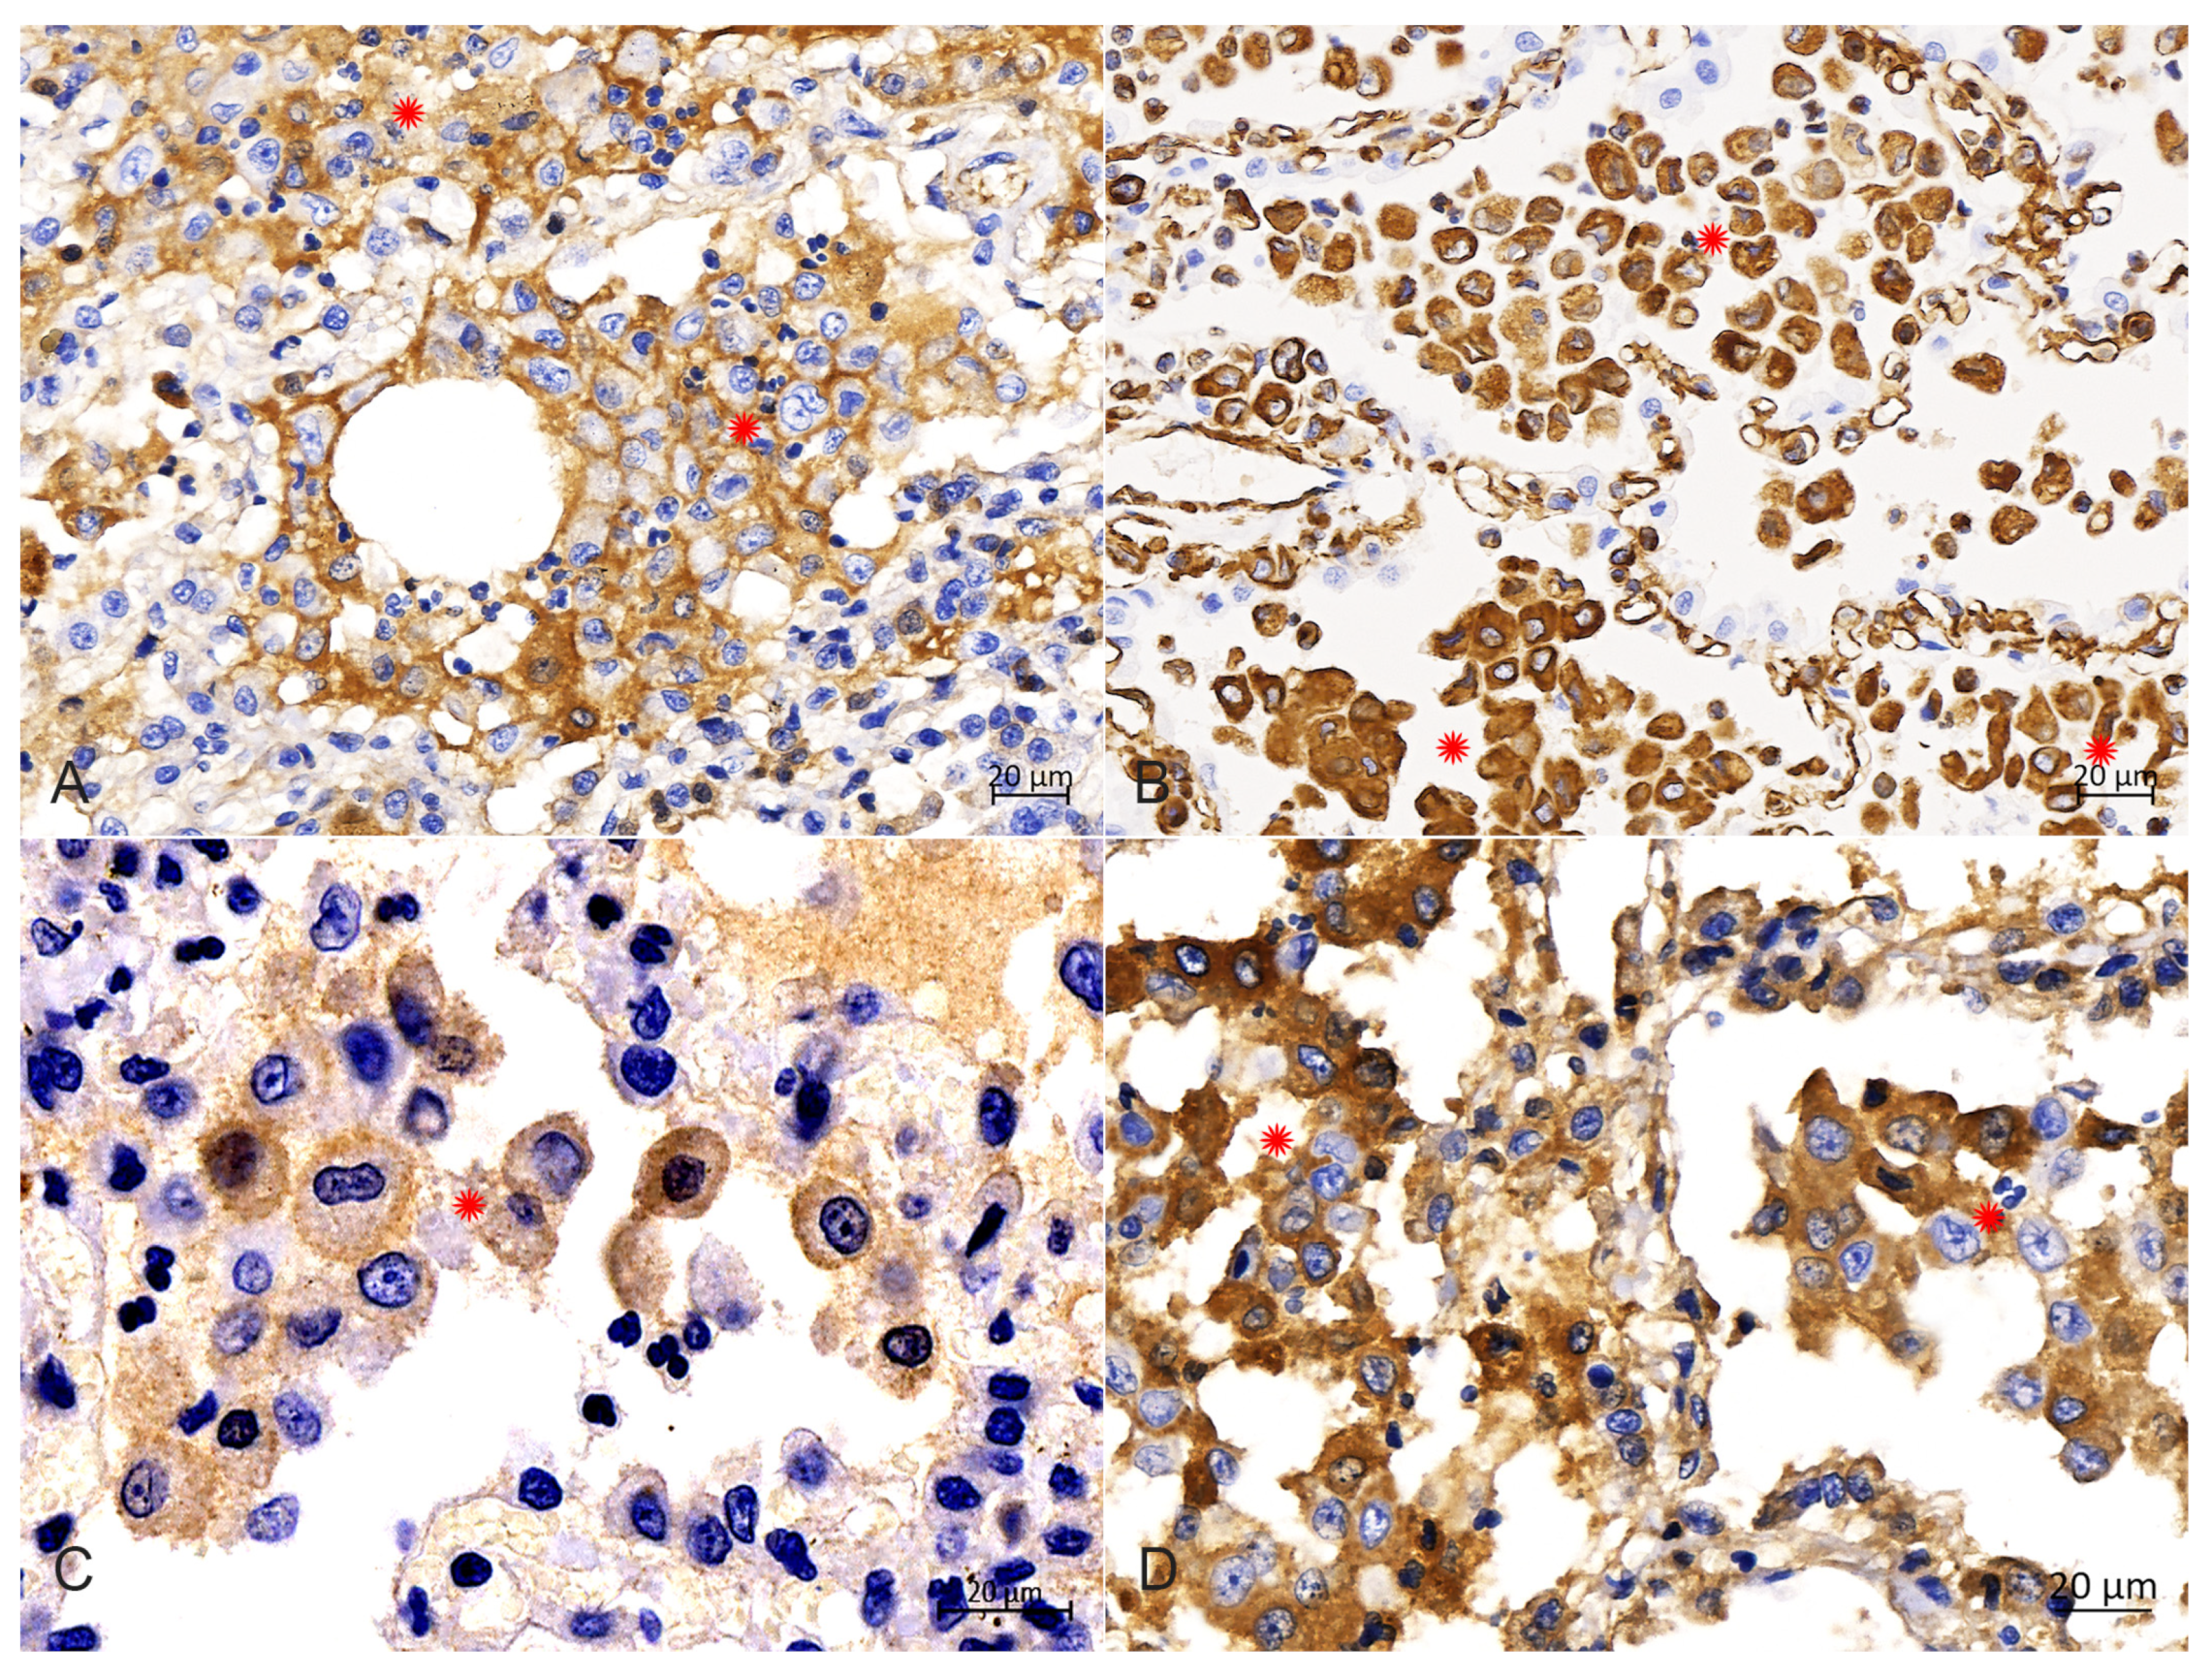

IHC analysis with diaminobenzidine staining and with all monoclonal antibodies (Abcarta) showed positive reactions for the monoclonal antibodies to CD1a (PA538; Figure 6A) in the membrane, and Vimentin (PA040; Figure 6B), S100 (PA139; Figure 6C) and E-cadherin (PA073; Figure 6D) in the cytoplasm of PHCs. Adverse reactions were observed for the monoclonal antibody to CD68. These data indicate that the PHCs were derived from LCs.

Figure 6.

Immunohistochemical analysis in the cytoplasm of PHCs. (A) Immunohistochemical staining of the CD1a was strongly positive in the membrane of PHCs (around asterisks), bar = 20 μm. (B) Immunohistochemical staining of vimentin was strongly positive in the cytoplasm of PHCs (around asterisks), bar = 20 μm. (C) Immunohistochemical staining of S100 was strongly positive in the intramembrane of PHCs (around asterisks), bar = 20 μm. (D) Immunohistochemical staining of E-cadherin was strongly positive in the cytoplasm of PHCs (around asterisks), bar = 20 μm.